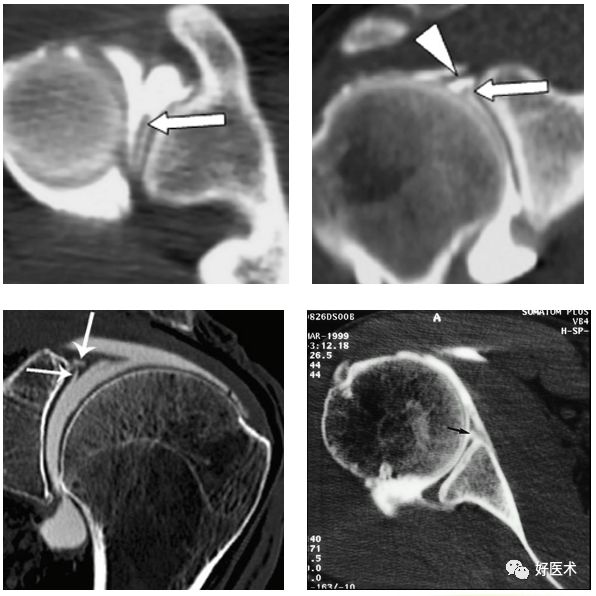

CT显示肩关节不稳

后脱位:反Hill-Sachs损伤

后关节盂撕脱小骨折

CT关节造影

-

显示盂唇损伤及关节囊韧带复合体损伤阳性率很高

为侵入性检查方式,有并发症

对软组织分辨率较低,需要加压注入空气使造影剂均匀弥散到组织表面

CT肩关节造影

Bankart损伤

Bankart 损伤指盂唇前下方在前下盂肱韧带附着处的撕脱性损伤

1938年Bankart首先描述了急性肩关节脱位导致创伤性关节盂唇剥脱

病因:肩关节前脱位后

前下盂唇损伤,可伴有相邻骨质(骨性Bankart)损伤,透明软骨、骨膜袖等损伤(Bankart 变异)

临床表现:疼痛,关节不稳,反复脱位

预后:复发性肩关节半脱位或脱位最常见的病理性损伤

Bankart损伤的MR表现

三角形变钝

盂唇撕裂:关节盂唇软骨与盂缘可见线状高信号影并连续到关节面下

盂唇完全消失或盂唇明显移位

若盂唇损伤合并关节盂骨质损伤,称为骨性Bankart病变

骨性Bankart病变

MR间接关节造影1.5T轴位T1W脂肪抑制(TR=460s,TE=90s)